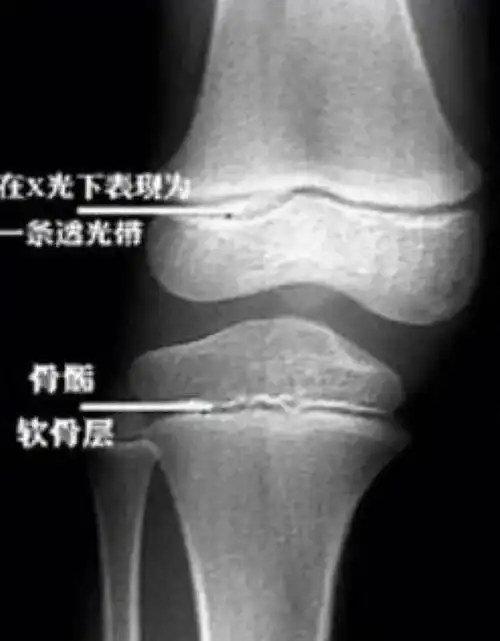

等骺板彻底骨化后 这个结果 也就是常说的 「骨骺线闭合」 所以 你

孩子的骨骼中有个部分叫作骨骺,这个东西在骨骼生长中至关重要.

骨骺线未闭合

长骨的最终长度也决定了成年后的身高,一般只要骨骺线未闭合,就还有

除了腿部,手部也同样存在的骨骺线.